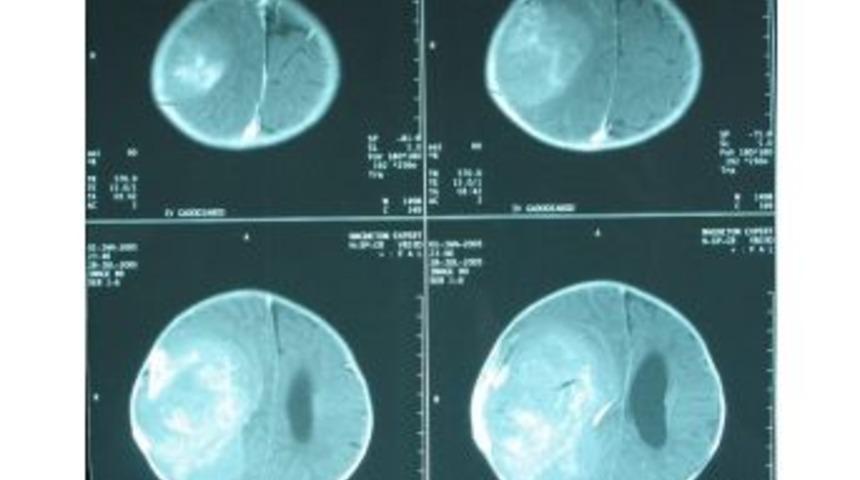

Bahçeşehir Üniversitesi Tıp Fakültesi öğretim üyesi, beyin ve sinir cerrahisi uzmanı Prof. Dr. Aslan Güzel, lösemi ve lenfomadan sonra çocuklarda en çok görülen beyin tümörlerinin erişkinlerden farklı belirtiler verdiği konusunda ebeveynleri uyardı.Dünya geneline bakıldığında çocukluk çağı kanserlerine bağlı ölümlerin yüzde 20’sinden sorumlu olan, Türkiye’de de durumun aynı seyrettiği, her 100 bin çocuktan beşinde görülen beyin tümörleri hakkında açıklama yapan Prof. Dr.Güzel, "Çocukluk çağında görülen beyin tümörleri erişkinlerden farklı tip, özellik gösterirler ve erişkinlere göre daha geç fark edilebilirler. Çocuğun kendini ifade edememesi, kafatası kemiklerinin erken kapanmaması gibi nedenler bulguların geç fark edilmesine neden olabilir. Kimi zaman diğer bazı hastalıklarda da görülebilen huzursuzluk, gelişme geriliği, kusma, bulantı gibi belirtiler çoğunlukla beyin tümörleri dışında başka hastalıkları da akla getirdiğinden erken teşhiste gecikmeye neden olabilir. Ancak, hastada kafa içi basınç artışı belirtileri başlamış ve sebat ediyorsa beyin tümörü tanısı yapılan tetkiklerle daha erken konabilir. Çocuklardaki belirti ve bulgular erişkinlere göre atipiktir. Bu nedenle tanı geç konabilir ve geçen süre içerisinde kafatası içindeki tümör de büyük hacim veya boyutlara varabilir. Ağırlıklı olarak kafatası arka çukuru orta hatta yerleşim gösterirler ve çoğu zaman beyin omurilik sıvı dolaşımını bozarak beyinde sıvı toplanması (hidrosefali) bulguları ile belirti verirler” dedi.Nadiren metastaz şeklinde de görülebilen beyin tümörleri, kafa içi basınç artışı; baş ağrısı, bulantı, kusma bulguları, havale, görme problemleri, kafatasında büyüme, gelişme geriliği, obezite, hormon dengesizlikleri gibi belirti ve bulguları olarak kendisini gösteriyor. Bazen de genel hastalıklarda görülebilen süregelen halsizlik, huzursuzlukta bu belirtilere eklenebiliyor. Ultrasonografi, bilgisayarlı tomografi (BT), manyetik rezonans görüntüleme (MRG) gibi tanı yöntemlerinden yararlanılarak teşhis konan hastalık, multidisipliner takip ve tedavi gerektiriyor. Genellikle kitle saptandıktan sonra ameliyatlık ise beyin ve sinir cerrahisi uzmanı tarafından yapılan müdahaleye daha sonra pediatrik onkolog (medikal ve radyasyon onkoloji), destek amaçlı psikolog, psikiyatrist ile birlikte ek tedavi ve takibin yapılması uygun görülüyor. Kesin teşhis, cerrahi sonrası patoloji sonucuna göre konuyor ve buna göre hasta periyodik aralıklarla izleme alınıyor.Günümüzde çocukluk çağı beyin tümörlerinin büyük çoğunluğunun cerrahi olarak çıkarılmaları mümkündür. Bir kısmı ise radyasyon veya gama knife tedavisiyle iyileşme gösteriyor. Cerrahi sonrası onkoloji bölümleriyle birlikte tedavi, takipleri sayesinde de yaşam süre ve kalitesi artıyor. Çeşitli hastalıklarda olduğu gibi çocukluk çağı beyin tümörlerinde de erken tanı ve tedavi çok önemlidir. Birçok hastada erken müdahale ile uzun ve kaliteli bir yaşam mümkün olabilir. Özellikle çocukluk çağı baş ağrıları ve sabahları olan kusmalar, kol ve/veya bacakta güçsüzlük gibi belirtiler varsa ailelerin zaman kaybetmeden hekime başvurmaları erken teşhis açısından önemlidir. Çocukların baş ağrısı şikâyetleri mutlaka dikkate alınmalı ve hekim tarafından değerlendirilmeli, sabahları olan bulantı, kusmalar kesinlikle ciddiye alınmalıdır.